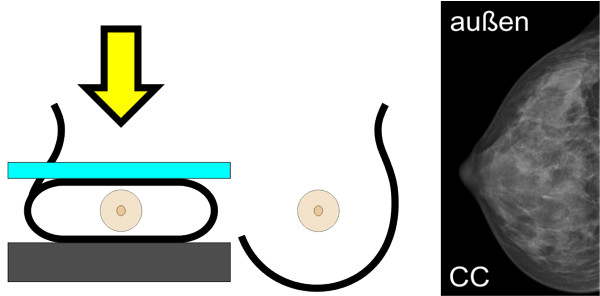

Von jeder Brust werden üblicherweise zwei Aufnahmen - jeweils von oben nach unten (cranio-caudale Aufnahme) und schräg von innen nach außen (medio-laterale oblique Aufnahme) - angefertigt. Die Brust wird dabei in eine Vorrichtung eingespannt und komprimiert:

Die cc-Aufnahme wird immer so dargestellt, dass die Außenseite der Brust im Bild oben liegt.

Viele Frauen empfinden die Druckbelastung durch die Kompression als sehr unangenehm. Unsere Röntgentechnikerinnen sind deshalb speziell darauf geschult, möglichst schonend und behutsam vorzugehen.

Die Kompression beeinflusst die Qualität der Aufnahme. Je dünner die Brust ausgestrichen ist, desto besser und klarer wird das Bild, wie das Beispiel unten zeigt.